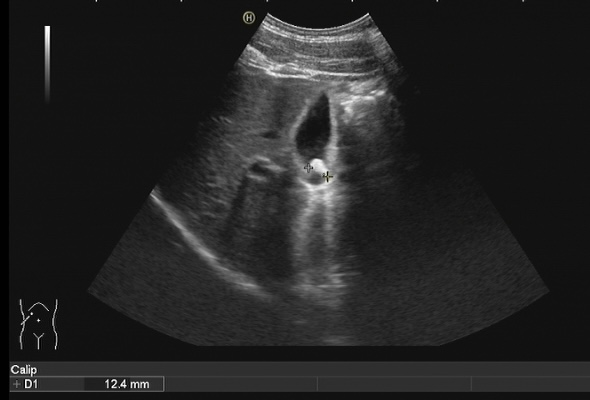

膽結(jié)石診斷方式很多,包括彩超、CT、核磁共振、膽管造影等方式都可以對(duì)膽道結(jié)石進(jìn)行診斷,但是彩超具有無(wú)創(chuàng)、無(wú)痛、無(wú)輻射、廉價(jià)、快速、可重復(fù)性強(qiáng)等優(yōu)點(diǎn),在臨床上被廣泛應(yīng)用作為膽結(jié)石的首選診斷方式。注意做肝膽彩超檢查必須要空腹,才能準(zhǔn)確檢查出膽道結(jié)石哦!

膽囊結(jié)石超聲圖像 | |